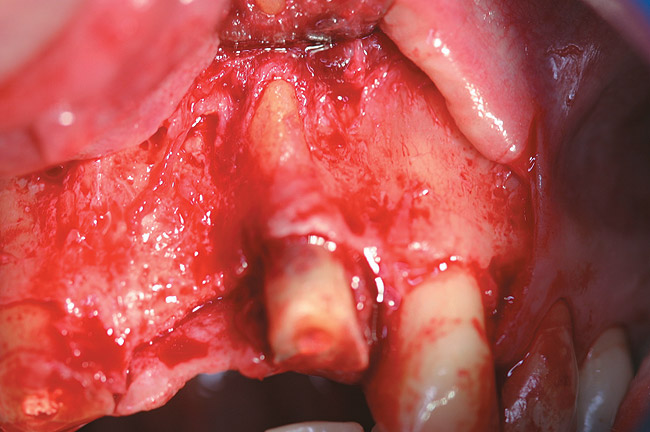

A full mucoperiosteal flap was reflected (Figure 1), and the residual roots of the two damaged teeth were extracted atraumatically, preserving the residual alveolar housing (Figure 2). Although thin, the facial plate was maintained to act as a supportive structure for the grafting material and membrane.

Figure 1  Full-thickness flap reflection exposed the left lateral incisor, which was fractured and intruded apically beyond the alveolar housing.

Figure 1